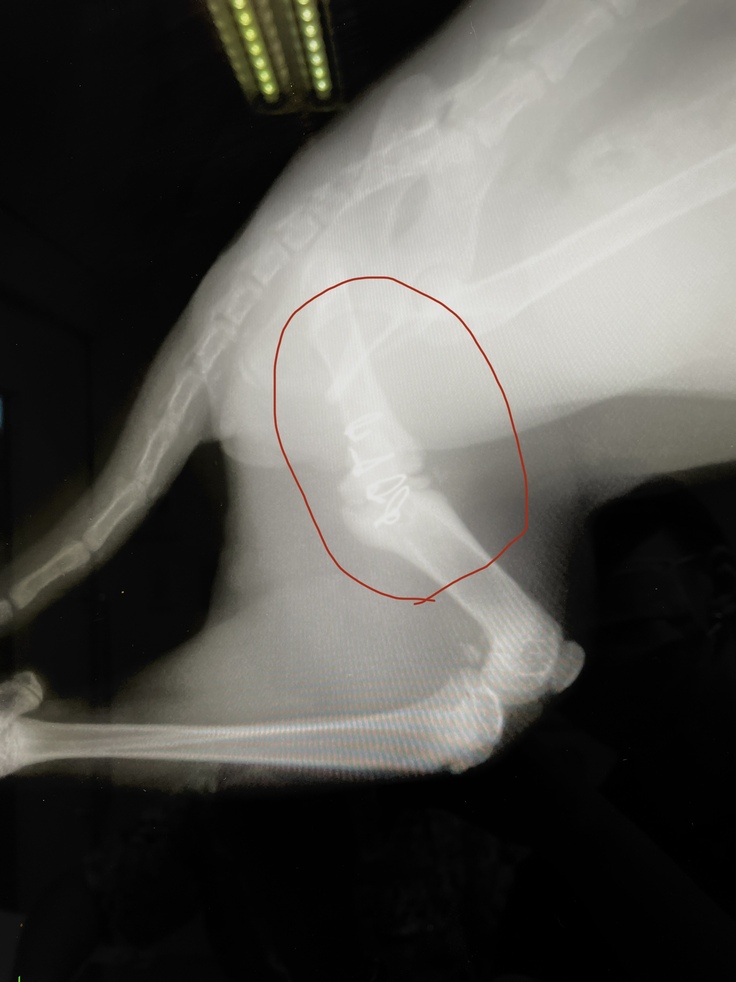

レントゲンの結果、左後脚大腿骨が3つに分かれていました。普通の骨折ではなく、粉砕骨折を患い、また腰骨も負傷している可能性があり、4本の足で立つことすら難しい状態でした。左後脚は力が入らず、ぶら下がってました。左後脚は手術が必要とのことで、すぐ手術の段取りをしました。

②手術&退院(8月20日〜8月21日)

8月20日に無事に手術が終わり、8月21日に退院しました。ステンレスのピンとワイヤーで骨を固定しています。服薬は難しいとのことで2週間効果が続く抗生剤の注射を退院時に接種しています。

8月20日に手術をした時には膝関節から大腿骨にかけてピンを入れてましたが、今はピンの位置がズレいて、お尻の皮膚が盛り上がり、突き破りそうになっています。

8月31日と9月11日に撮ったレントゲンを比べても、かなりピンの位置が違います。